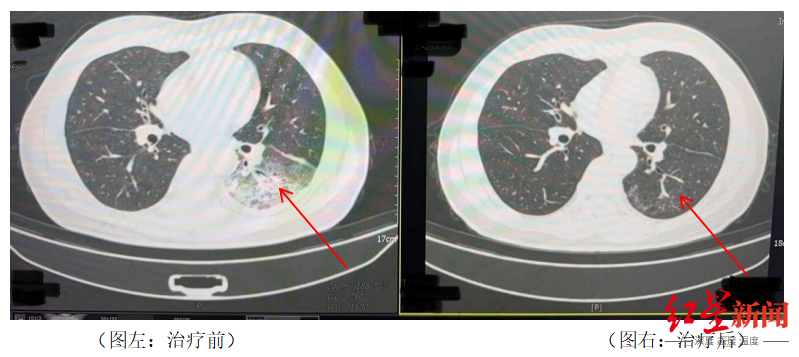

李先生肺部治疗前与治疗后的对比

据悉,开启空调降温3天后,李先生出现了肌肉酸痛、头痛、发热和咳嗽等症状。起初,他以为是吹空调吹感冒了,于是自行服用感冒药,但病情并未好转,反而愈发严重。家人见状,立即将他送往成都市第五人民医院感染性疾病科。胸部CT显示李先生的左肺已出现大面积白色影像,几乎占据一半肺部。经过肺泡灌洗NGS检测,最终确认“罪魁祸首”是嗜肺军团菌